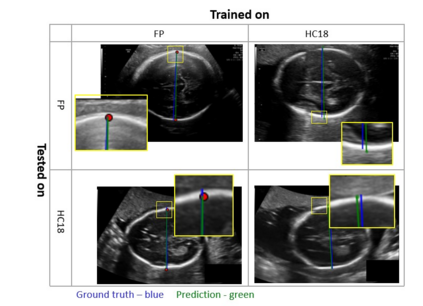

Fetal growth assessment from ultrasound is based on a few biometric measurements that are performed manually and assessed relative to the expected gestational age. Reliable biometry estimation depends on the precise detection of landmarks in standard ultrasound planes. Manual annotation can be time-consuming and operator dependent task, and may results in high measurements variability. Existing methods for automatic fetal biometry rely on initial automatic fetal structure segmentation followed by geometric landmark detection. However, segmentation annotations are time-consuming and may be inaccurate, and landmark detection requires developing measurement-specific geometric methods. This paper describes BiometryNet, an end-to-end landmark regression framework for fetal biometry estimation that overcomes these limitations. It includes a novel Dynamic Orientation Determination (DOD) method for enforcing measurement-specific orientation consistency during network training. DOD reduces variabilities in network training, increases landmark localization accuracy, thus yields accurate and robust biometric measurements. To validate our method, we assembled a dataset of 3,398 ultrasound images from 1,829 subjects acquired in three clinical sites with seven different ultrasound devices. Comparison and cross-validation of three different biometric measurements on two independent datasets shows that BiometryNet is robust and yields accurate measurements whose errors are lower than the clinically permissible errors, outperforming other existing automated biometry estimation methods. Code is available at https://github.com/netanellavisdris/fetalbiometry.